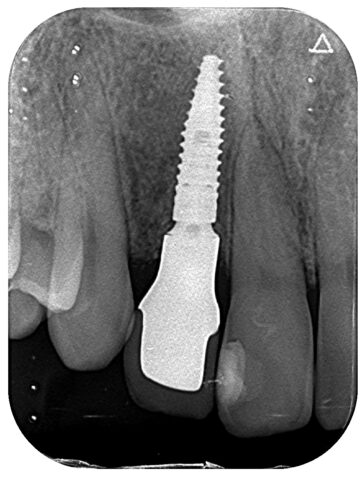

症状 上顎右側側切歯のう蝕、歯根破折による変色 年齢・性別 20代女性 治療期間 4か月 治療方法 上顎右側側切歯がコンポジットレジンの二次カリエスのため歯根内までう蝕が広がっており、審美障害と歯根の破折をきたしており、予後不良と判断した。 抜歯を行ったと同時にBLTインプラント埋入を行い、骨増生と軟組織の移植を行った。 上部はジルコニアクラウンをスクリュー固定した。 費用 55万円 デメリット・注意点 保険適応外治療。 骨増生、軟組織移植を必要とする。 -